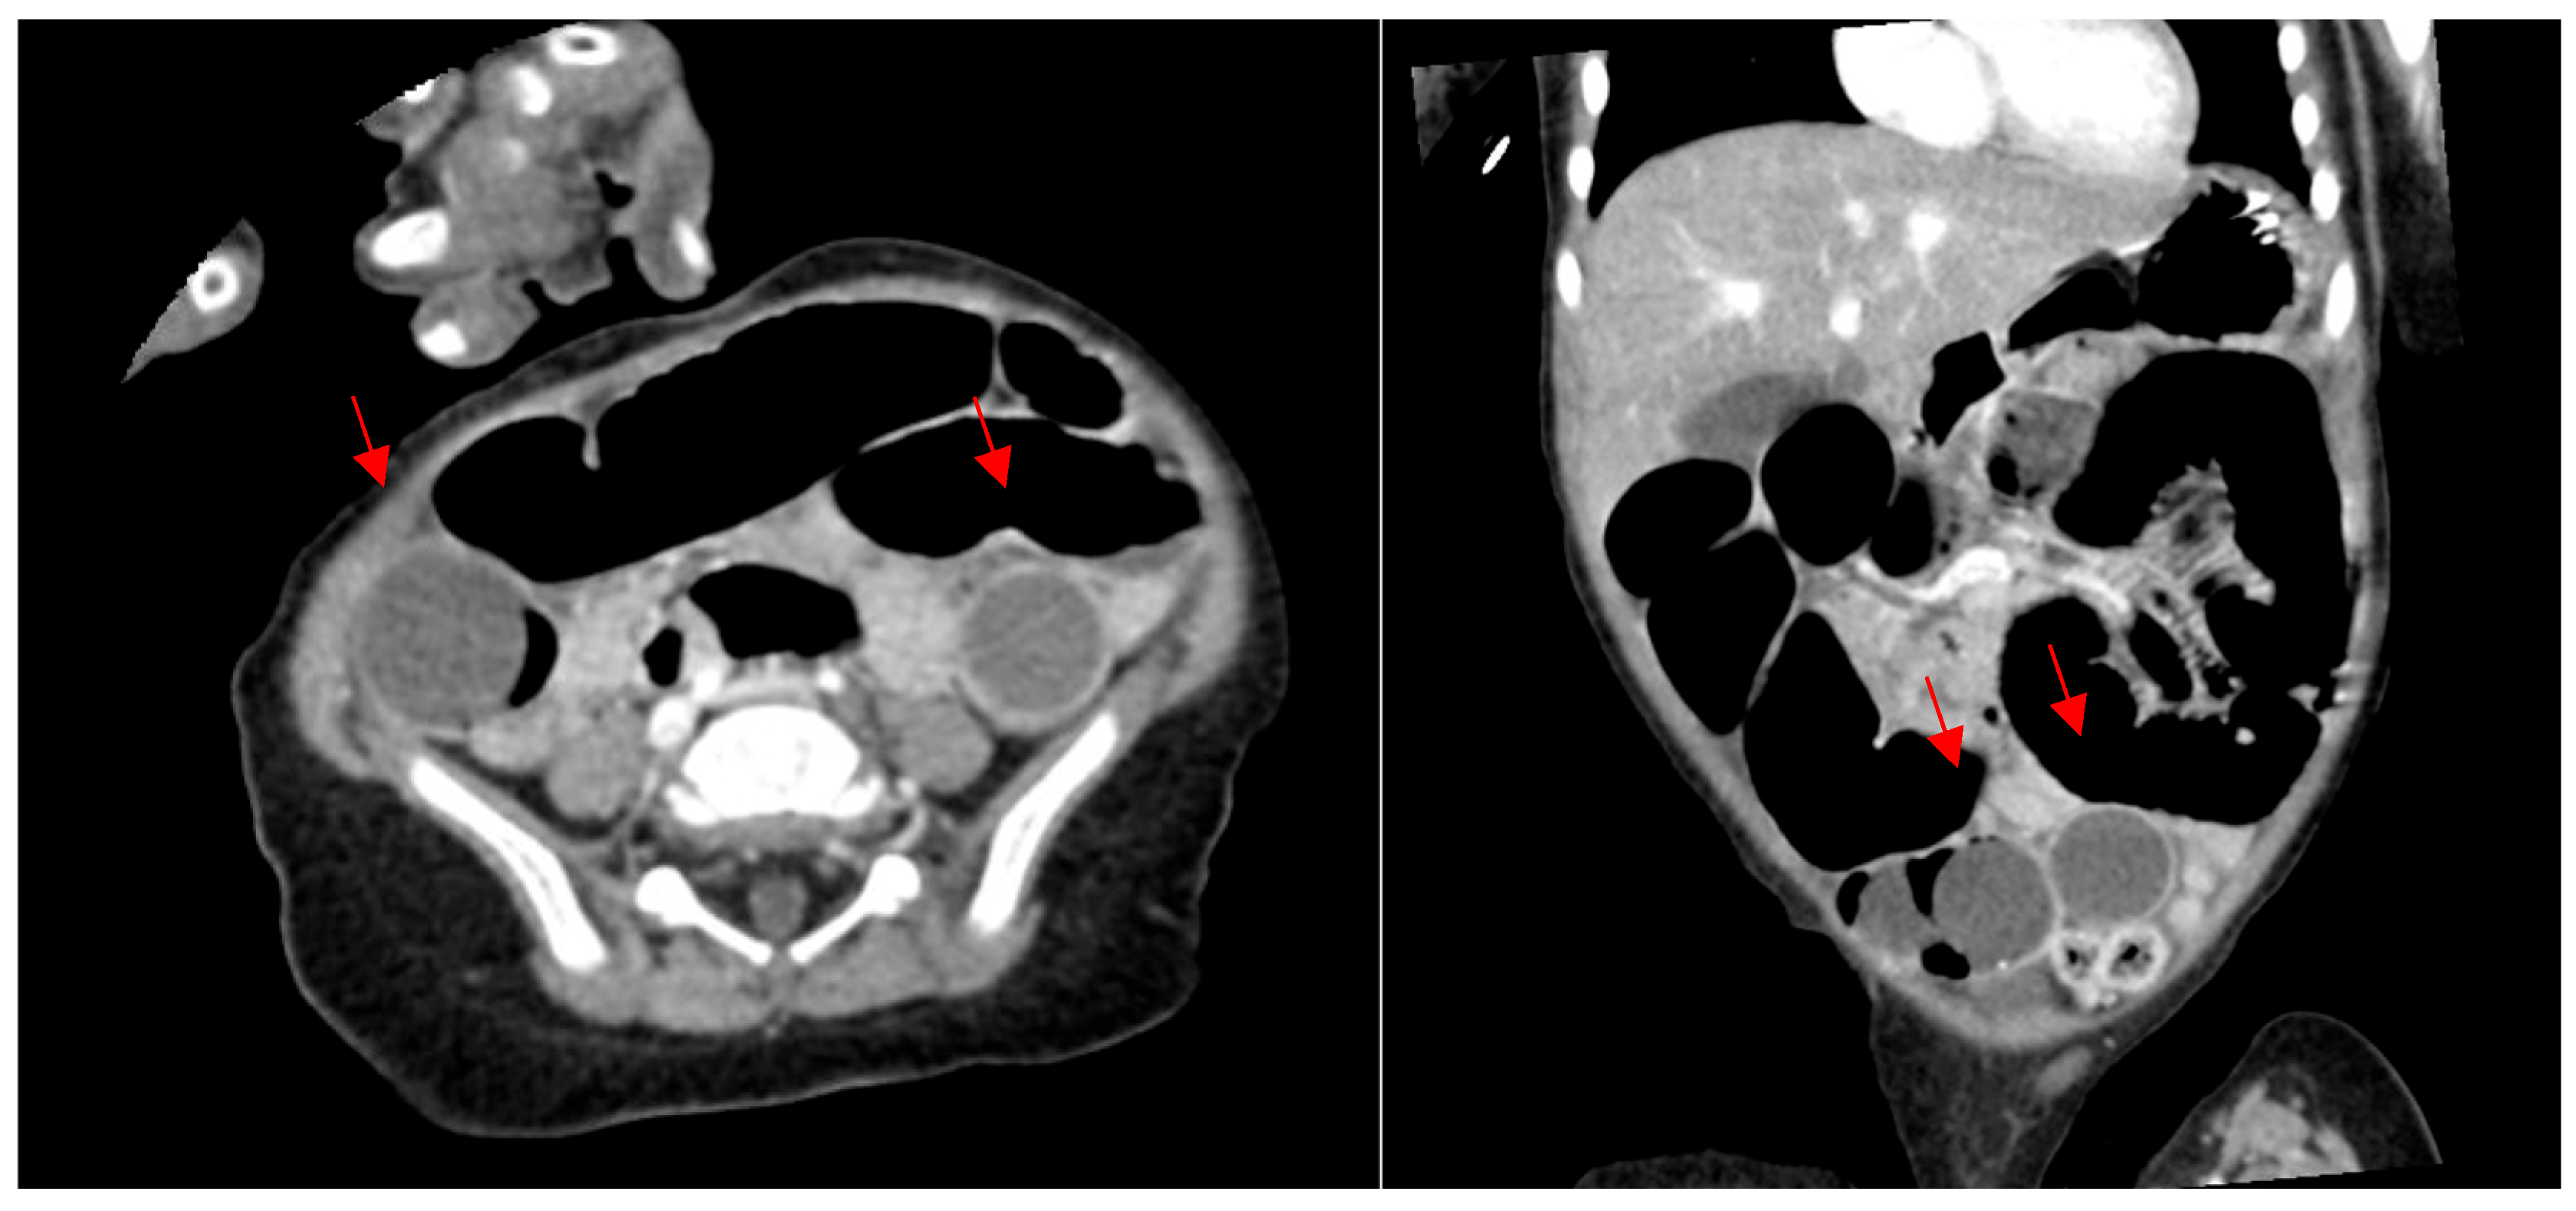

3.1. Patient 1

3.2. Patient 2